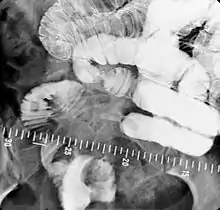

For small bowel examinations, in addition to fasting for 8 hours prior to examination, a laxative may also be necessary for bowel preparation and cleansing.[11] Enteroclysis involves the continued infusion of 500 to 1000 mL of thin barium sulfate suspension into the intestine through a duodenal tube. Then methylcellulose is instilled through the tube. Barium and methylcellulose fill the intestinal loops which can be viewed continuously using fluoroscopy, or viewed as standard radiographs taken at frequent intervals. The technique is a double-contrast procedure that allows detailed imaging of the entire small intestine. However, the procedure may take 6 hours or longer to complete and is quite uncomfortable to undergo.[17]

- Enteroclysis has shown to be very accurate in diagnosing small bowel diseases, with a sensitivity of 93.1% and specificity of 96.9%. It permits detection of lesion which may not be seen with other imaging techniques.[7] There is no significant difference in terms of detection of clinically significant findings, sensitivity or specificity between enteroclysis and CT enterography.[1] Enteroclysis compares favorably with wireless capsule endoscopy and double-balloon endoscopy in the diagnosis of mucosal abnormalities of the small bowel.[18]

- Enteroclysis, also called small bowel enema, is a barium X-ray examination used to display individual loops of the small intestine by intubating the jejunum and administering barium sulfate followed by methylcellulose or air.[5]